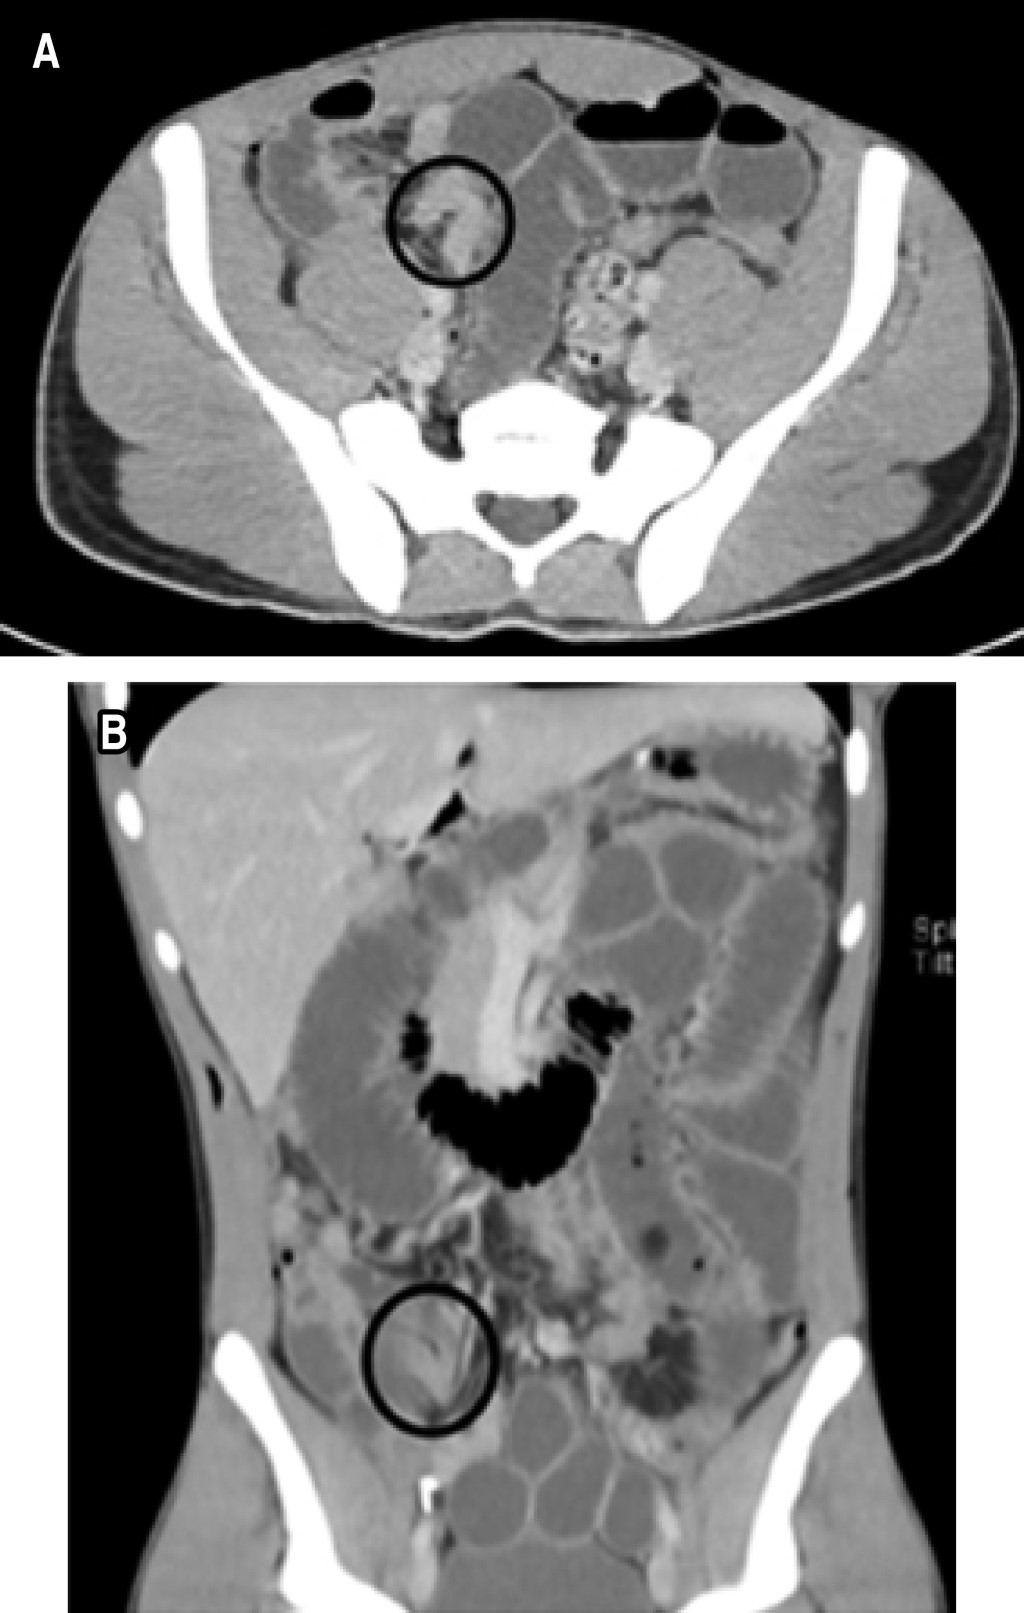

The patient was admitted for observation, intravenous hydration with lactated Ringer's solution was administered, and symptomatic medical management was instituted, persisting with symptomatology, for which the placement of a nasogastric tube (NGT) and a computed tomography (CT) scan of the abdomen with intravenous contrast was indicated. The abdominal CT scan demonstrated a small bowel obstruction with a suspected internal hernia (Figure 1). Based on clinical and radiological findings, it was decided to perform an emergency diagnostic laparoscopy. A small bowel loop herniated into the preperitoneal space through a peritoneal defect was identified as the origin of the obstruction (Figure 2). No evidence of loop distress was identified, so the hernia was reduced, and subsequent closure of the peritoneal defect with polyglactin 910 2-0 cross-stitches was done.

Figure 2